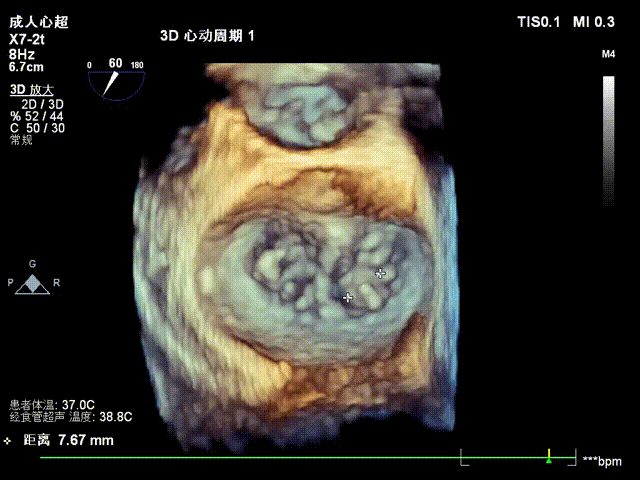

术前影像

手术难点/病例特征

该病例为二尖瓣重度反流,前叶A3区瓣叶脱垂并并腱索断裂,后叶瓣叶合并钙化,捕获瓣叶有一定难度。拟植入一枚NeoNova®C6(宽6mm)夹合器于3区脱垂处解决主要脱垂,然后根据残余反流和瓣口面积条件判断是否需要植入第二枚夹合器。